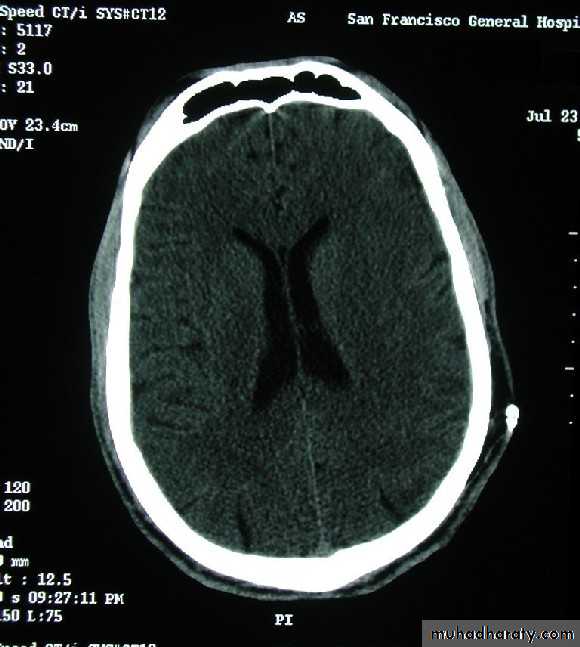

B-Brain oedema

NORMAL & OEDAMATOUS BRAIN